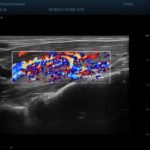

Lesione della cuffia dei rotatori

Paziente con dolore alla spalla dx,all’es.ecografico versamento nella borsa subacromialee lesione del tendine sovraspinato ben evidente anche se piccola L’esame ecografico ha il vantaggio rispetto alla risonanza magnetica che è dinamico,si fa anche muovendo attivamente e passivamente l’articolazione dlela spalla